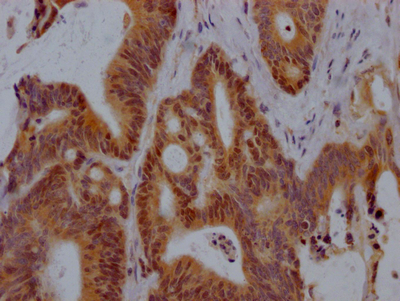

應用范圍:ELISA, IHC, IF

Application Recommended Dilution IHC 1:20-1:200 IF 1:50-1:200 -